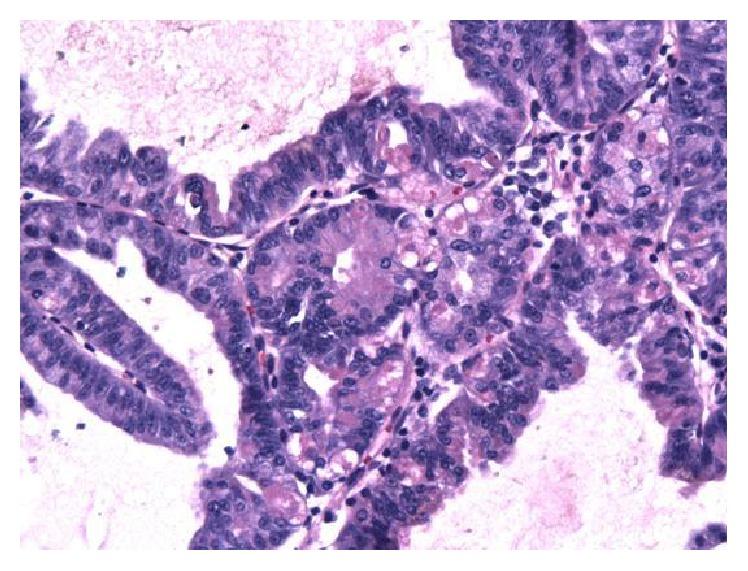

Gastric adenocarcinoma of the fundic gland type (GA-FG) is a rare entity that has only recently been described and defined. There is ongoing controversy regarding the malignant potential of this lesion. We report the case of a GA-FG in a 49-year-old Caucasian man who was referred to endoscopy for management of an incidentally found gastric polyp. Endoscopy showed a single polypoid lesion in the gastric fundus which was successfully removed with endoscopic resection. Grossly, the polyp measured 1.1 cm in greatest dimension. Microscopic examination showed irregularly branched neoplastic glands covered with a nonneoplastic foveolar epithelium. The continuity between the neoplastic glands and the fundic glands is clearly identified, indicating the tumor arose from the fundic glands. The tumor cells exhibited occasional oxyntic cytoplasm with enlarged atypical nuclei. The tumor invaded the submucosa with complete disruption of the muscularis mucosae and mild lymphocytic and fibroblastic stromal reaction. No necrosis, mitosis, or lymph-vascular invasion was identified. Although some authors have proposed reclassification of GA-FGs as oxyntic gland polyps/adenomas, in light of several reported cases with submucosal invasion as well as lymphatic invasion, we maintain that this neoplasm is best categorized as an extremely well-differentiated adenocarcinoma to reflect its invasive potential.

胃底腺型胃癌(GA - FG)是一种罕见的疾病,直到最近才被描述和定义。关于这种病变的恶性潜能存在持续的争议。我们报告了一例49岁白种男性的GA - FG病例,该患者因偶然发现的胃息肉接受内镜检查。内镜检查显示胃底有一个单个息肉样病变,通过内镜切除成功切除。大体上,息肉最大直径为1.1厘米。显微镜检查显示有不规则分支的肿瘤性腺体,表面覆盖非肿瘤性的小凹上皮。肿瘤性腺体与胃底腺之间的连续性清晰可辨,表明肿瘤起源于胃底腺。肿瘤细胞偶尔可见壁细胞样细胞质,核增大且异型。肿瘤侵犯黏膜下层,黏膜肌层完全破坏,伴有轻度淋巴细胞和纤维母细胞性间质反应。未发现坏死、核分裂或淋巴血管侵犯。尽管一些作者提议将GA - FG重新分类为壁细胞性腺息肉/腺瘤,但鉴于有几例报告显示存在黏膜下侵犯以及淋巴侵犯,我们认为这种肿瘤最好归类为高分化腺癌,以反映其侵袭潜能。